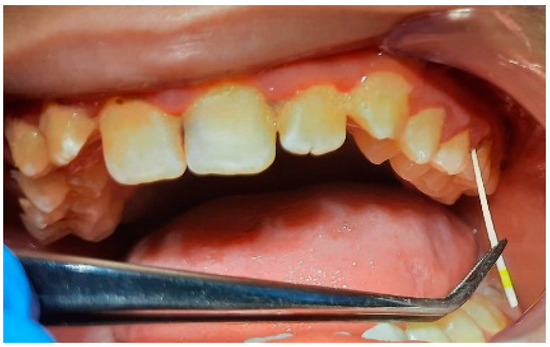

2.2. Clinical Examinations

2.3. Sampling for PCR

3.2. Analysis of Clinical Data